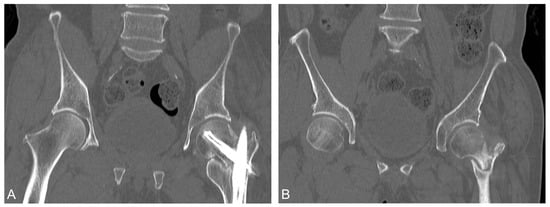

2. Case Report